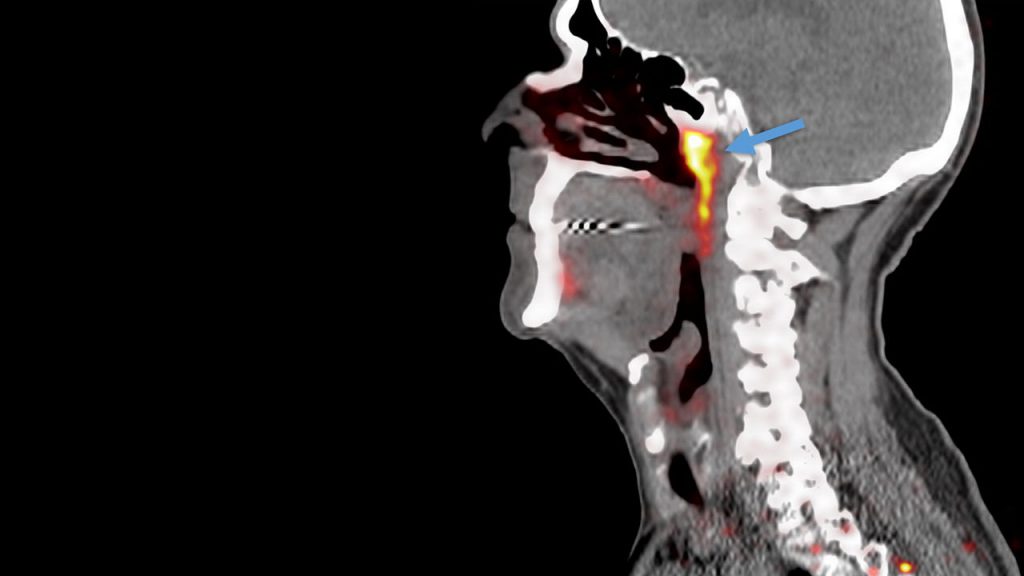

Burun boşluğunun boğazla birleştiği yerde bulunan söz konusu yapı, prostat veya üretral bez kanseri teşhisi konmuş 100 hastanın bilgisayarlı tomografi taramaları incelenirken tespit edildi. Daha sonra iki kadavradan dokuların incelenmesiyle yapıların ağız tabanında bulunan tükürük bezlerine benzer olduğunu görüldü.

Bu yapıların yeni keşfedilen organlar mı yoksa ağız ve boğazdaki yüzlerce küçük tükürük bezinden biri mi olduğu sonucuna varmak için daha fazla araştırmaya ihtiyaç olduğu ifade ediliyor. Bulgu doğrulanırsa, yaklaşık 300 yıllık aradan sonra keşfedilen ilk tükürük bezi olacak.